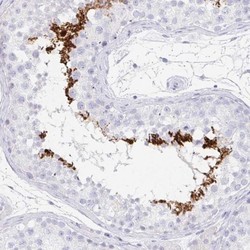

- Immunohistochemistry-Paraffin: C2orf57 Antibody [NBP2-14406] - Staining of human kidney shows low expression as expected.